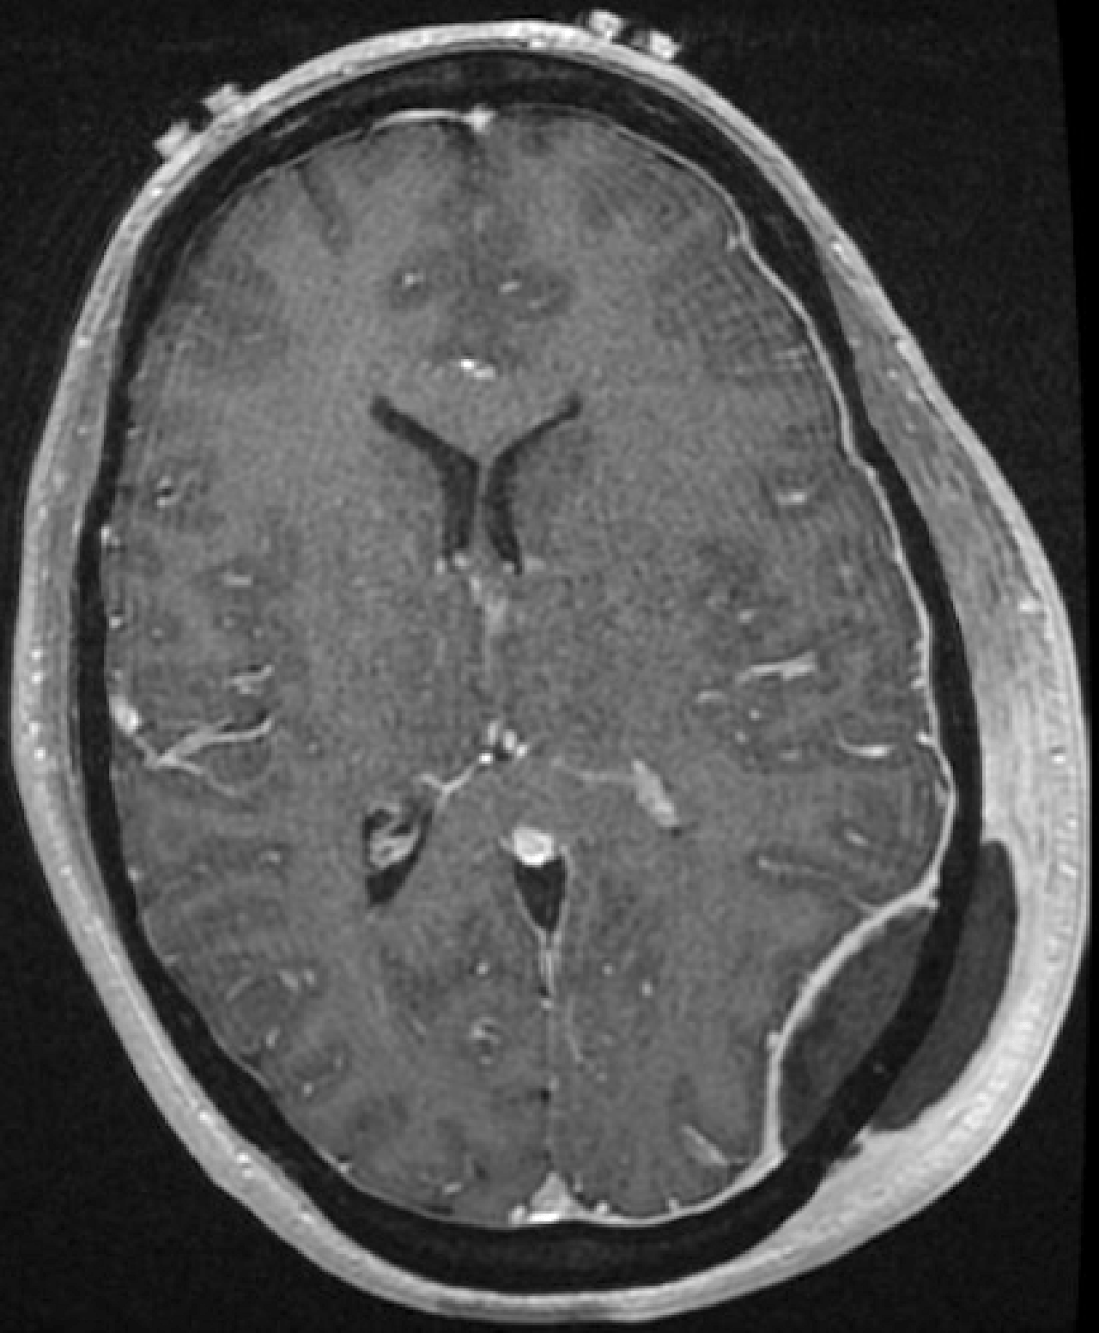

Cranial epidural abscess

Inspired by Priola et al 2019.[1] This is the first reported case of a cranial epidural abscess as a likely complication of acupuncture treatment. The report was written by the specialist neurosurgical team under whom the patient was admitted. This is often the case in such unusual and serious adverse events, but it also limits … Continue reading Cranial epidural abscess